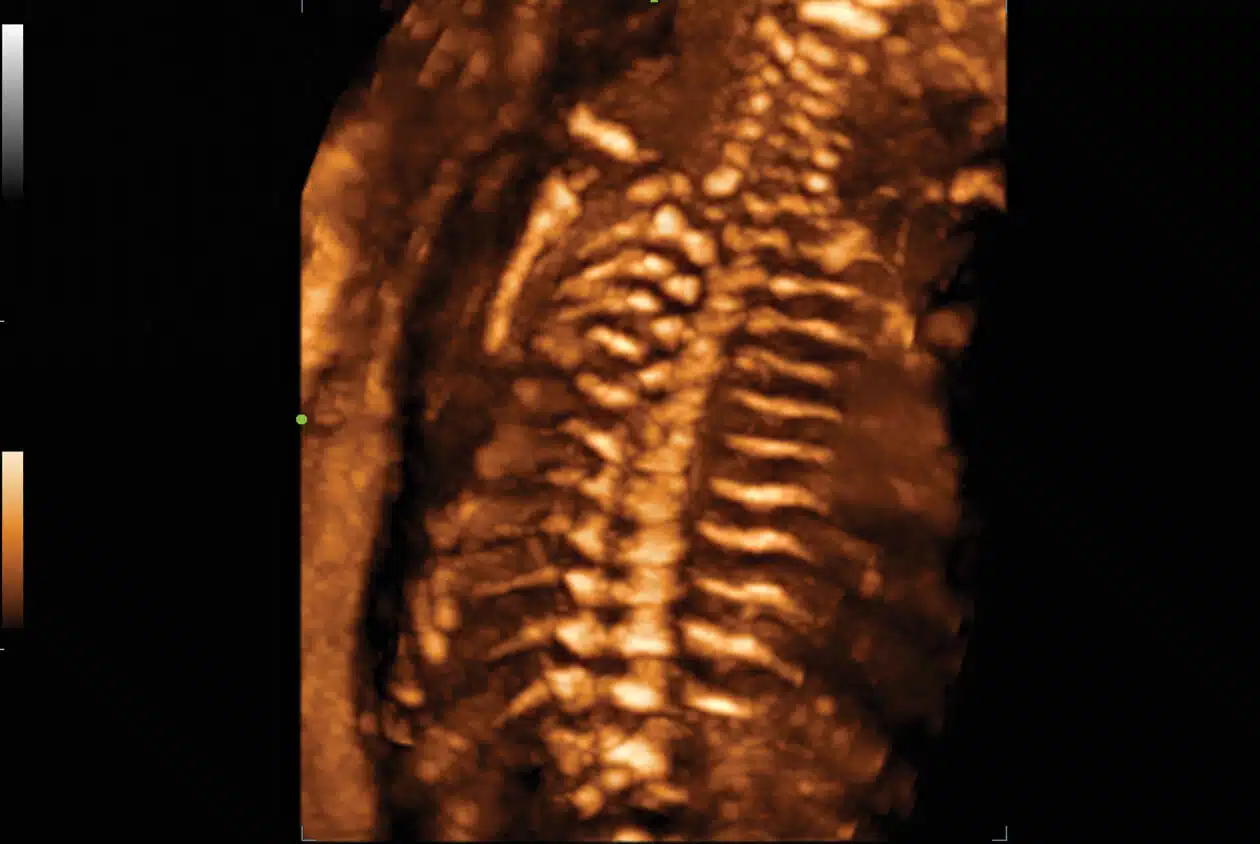

• SD8-1s-Fetal-Spine-3D1.jpg

3D Imaging of the Fetal Spine